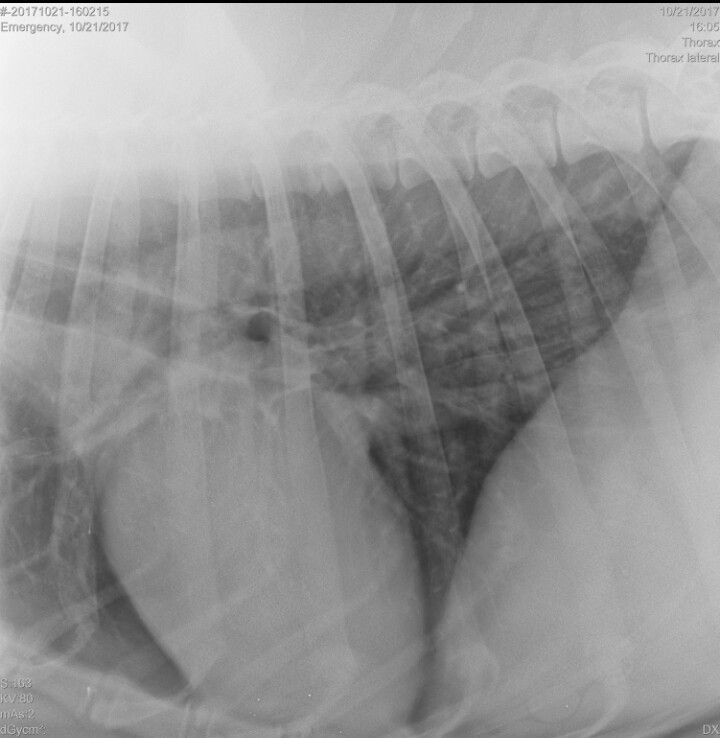

Остеосаркома проксимального отдела правой плечевой кости, после операции и 4х курсов МХТ в 2020 г. Рецидив опухоли в 2021 г. (множественные mts в лёгких, ребрах, подвздошных костях, в поясничном отделе позвоночника (L5) с компрессией спинного мозга и блоком фораминального отверстия на уровне L4-5 справа) .